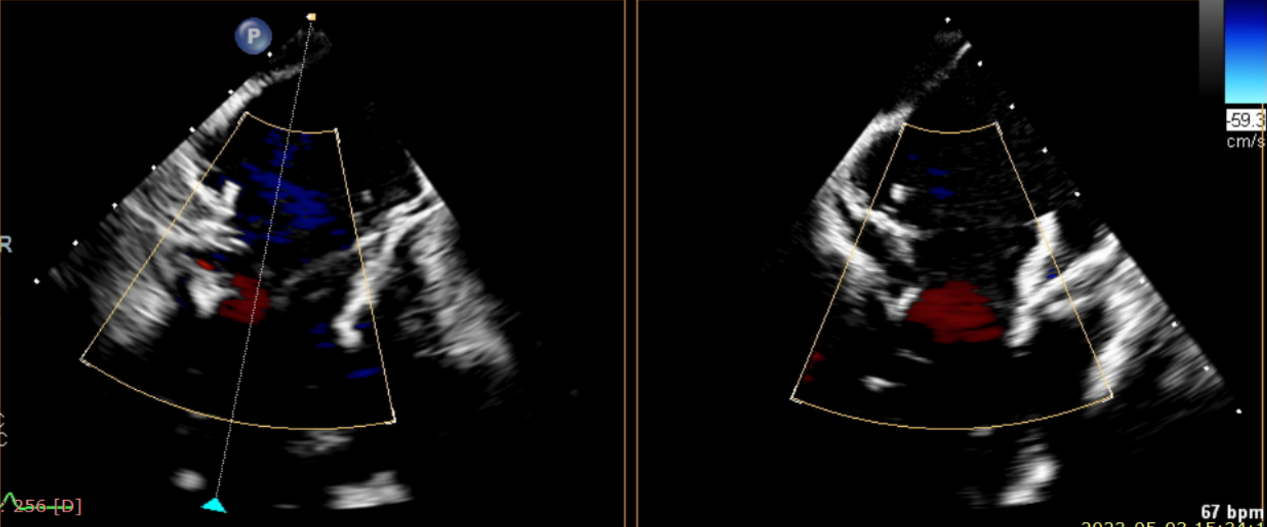

術(shù)后超聲提示無瓣周漏

術(shù)后超聲提示僅殘余輕微瓣周漏